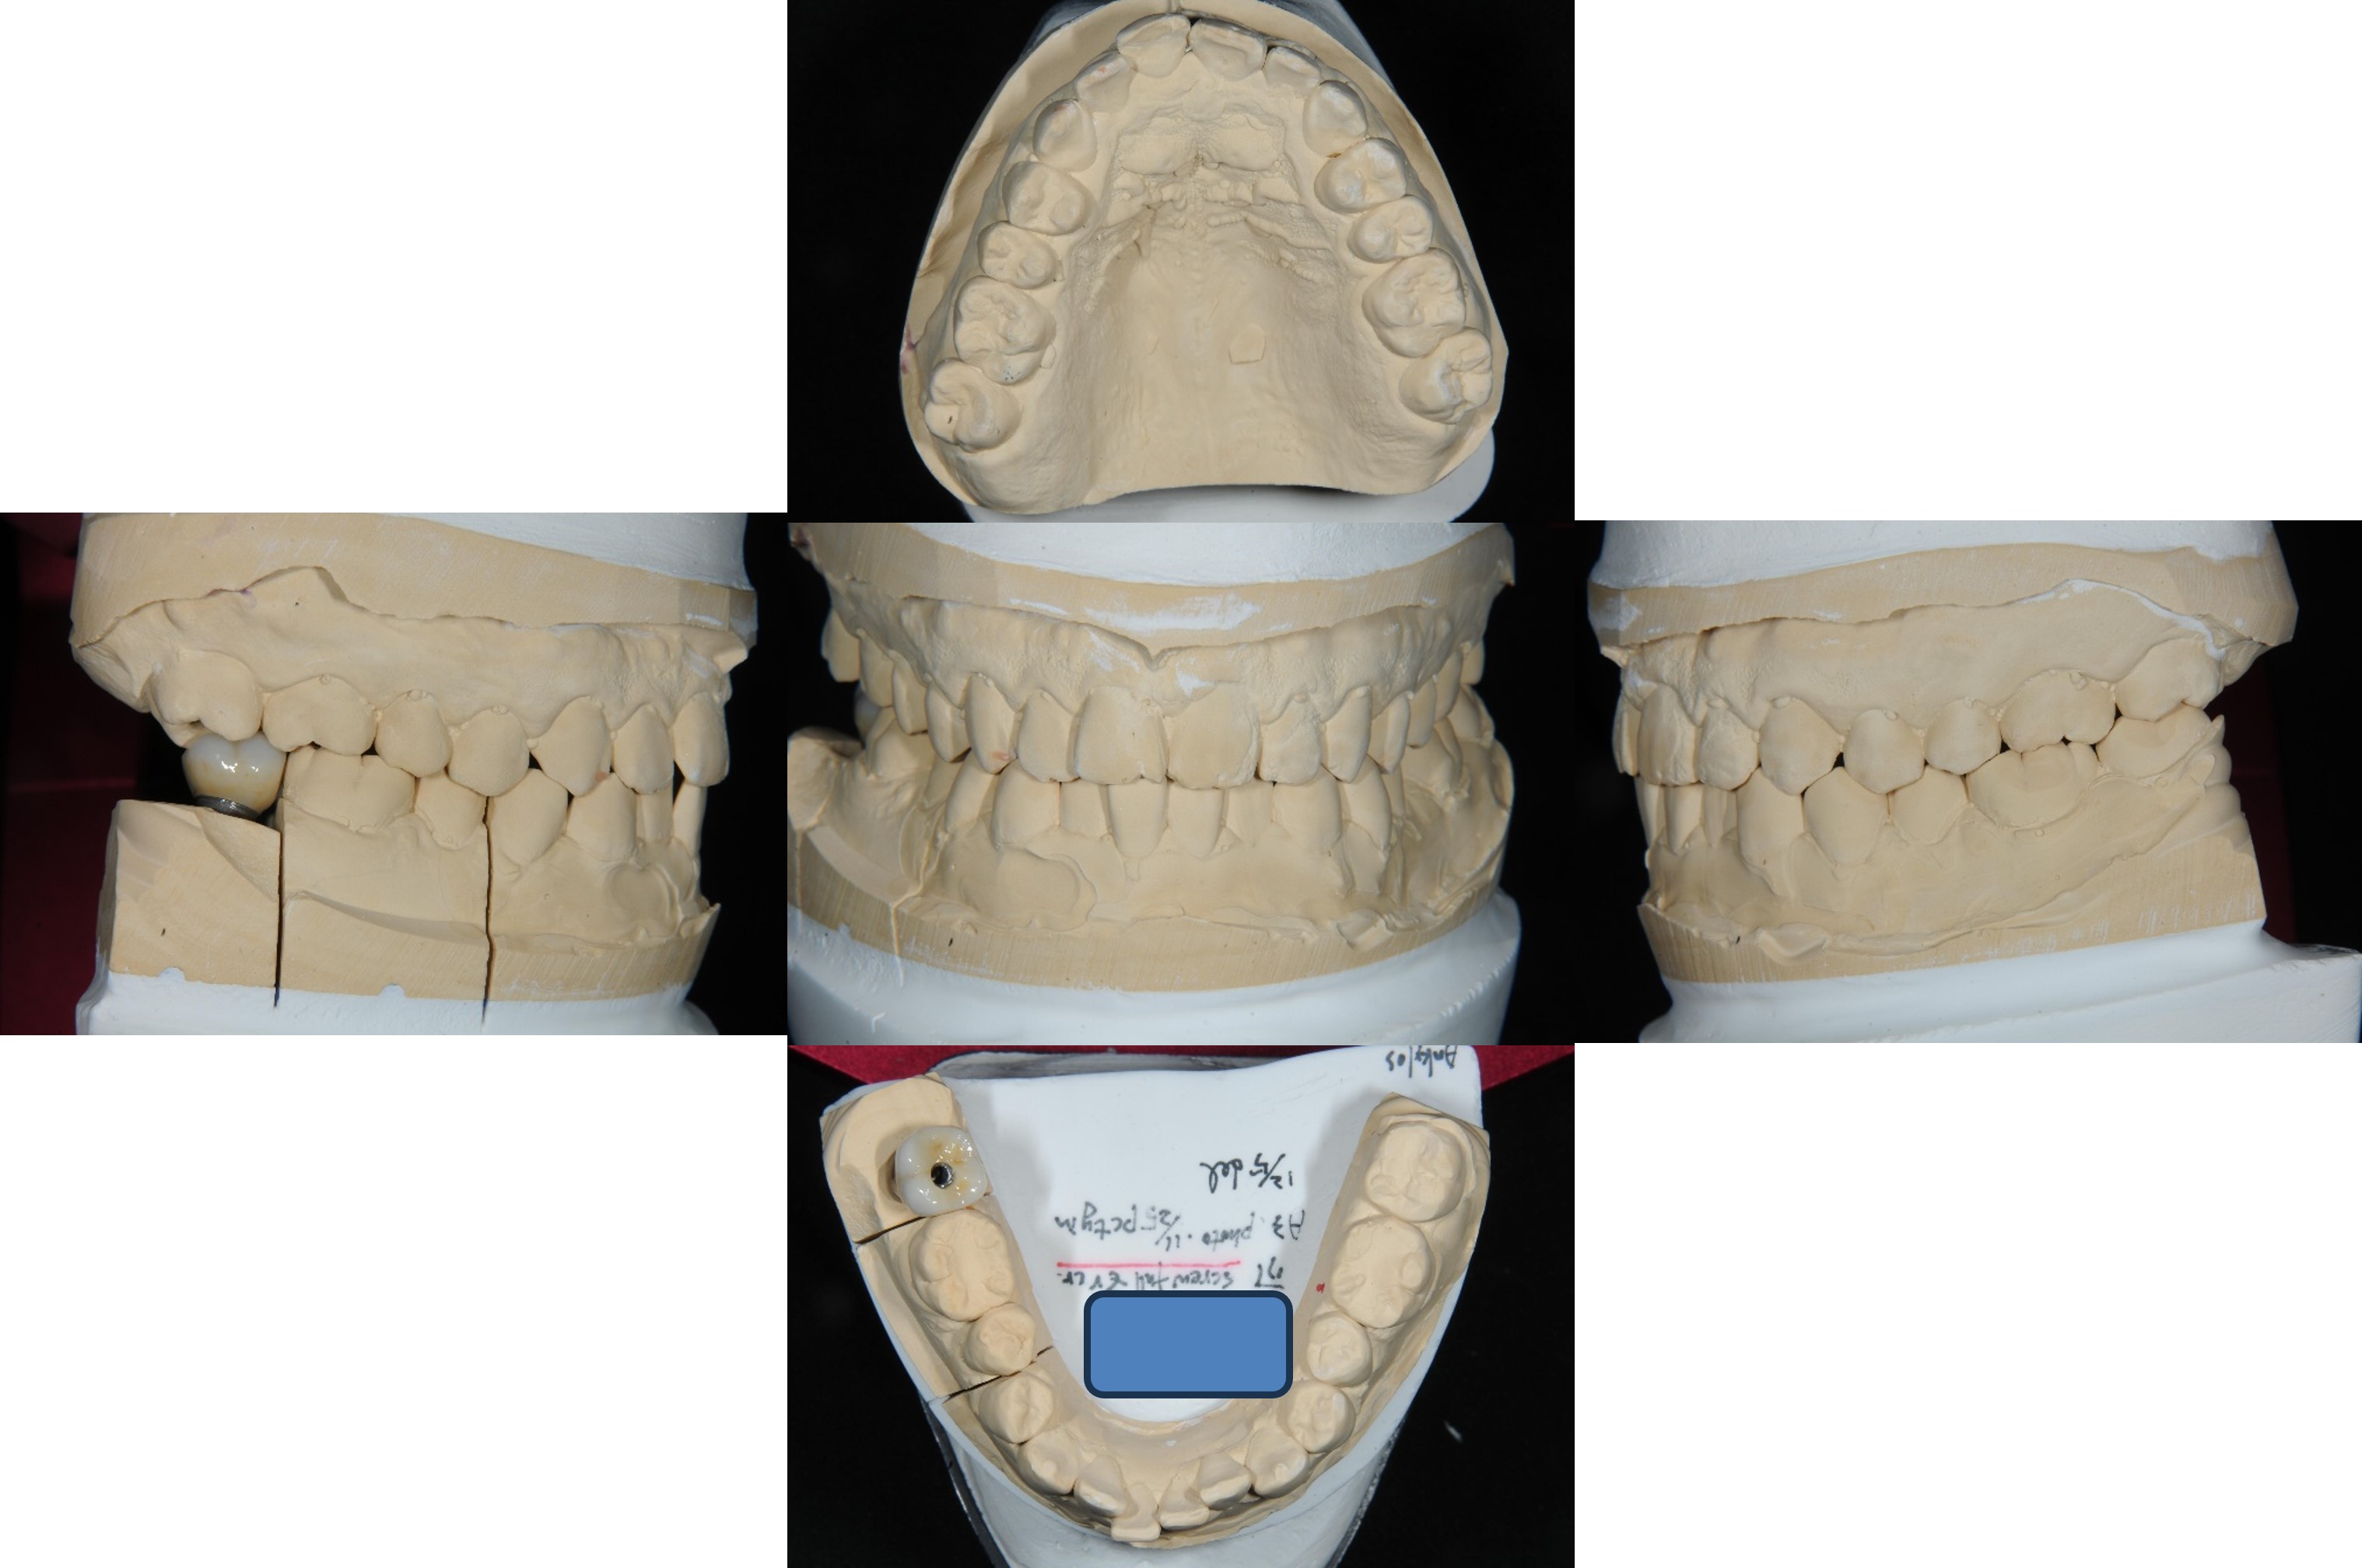

面弓轉移,上咬合器

咬合器上製作瓷牙